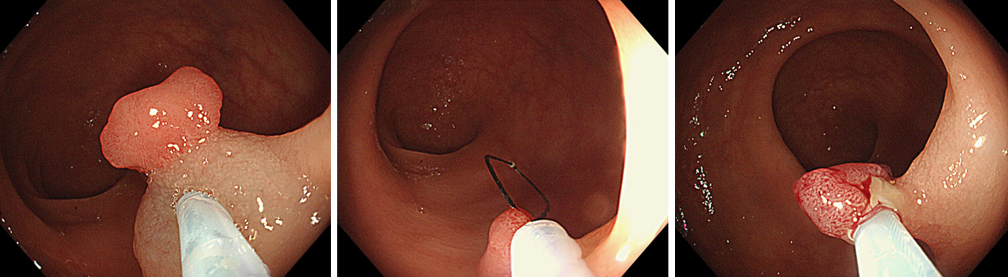

一般的には大腸カメラ検査と呼ばれている大腸内視鏡検査は、肛門から細長いスコープを入れて直腸から結腸、盲腸のほか、小腸の回腸末端までを直接観察できます。そのため微小な病変も見つけやすく、高精度な検査です。